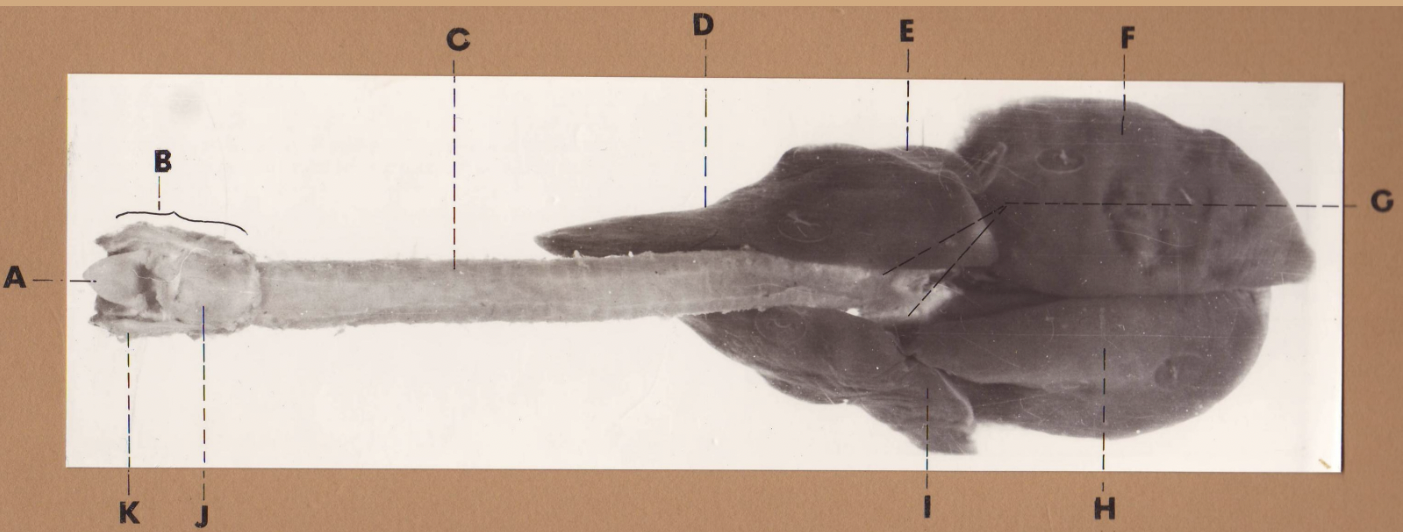

A

(cat larynx/trachea/lungs, dorsal)

epiglottis

B

(cat larynx/trachea/lungs, dorsal)

larynx

C

(cat larynx/trachea/lungs, dorsal)

trachea

D

(cat larynx/trachea/lungs, dorsal)

R cranial lobe

E

(cat larynx/trachea/lungs, dorsal)

middle lobe

F

(cat larynx/trachea/lungs, dorsal)

R caudal lobe

G

(cat larynx/trachea/lungs, dorsal)

primary bronchi

H

(cat larynx/trachea/lungs, dorsal)

L caudal lobe

I

(cat larynx/trachea/lungs, dorsal)

L cranial lobe

J

(cat larynx/trachea/lungs, dorsal)

cricoarytenoideus dorsalis m

K

(cat larynx/trachea/lungs, dorsal)

thyroid